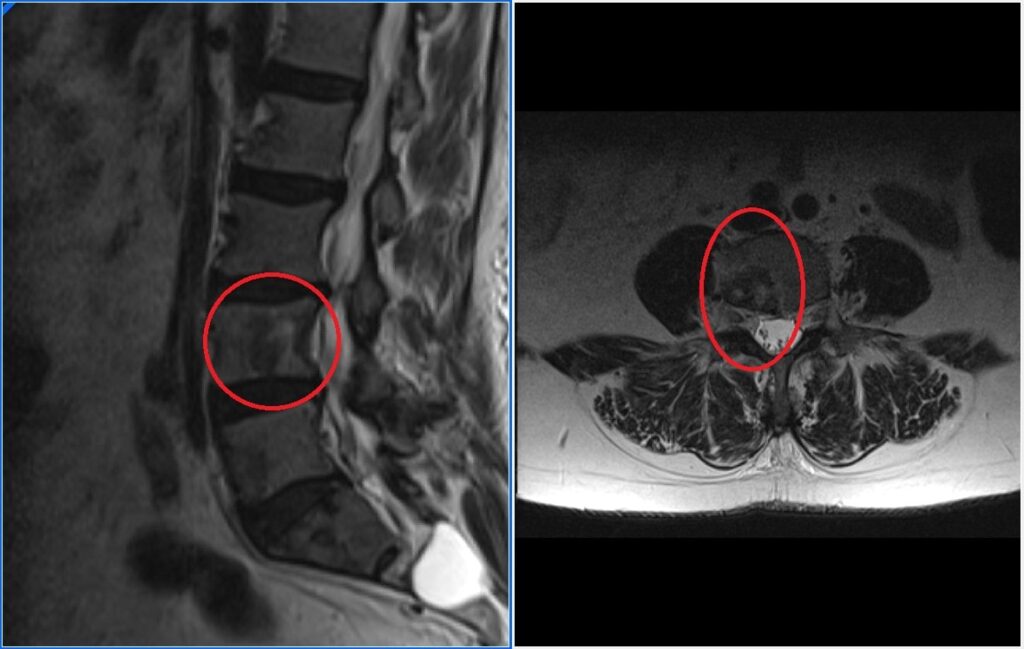

Existen dos vías principales del dolor: la vía rápida y la vía lenta. La vía rápida transmite señales agudas y punzantes, mientras que la vía lenta lleva señales sordas y persistentes. Estas señales viajan desde la médula espinal hasta diferentes áreas cerebrales, incluyendo la corteza somatosensorial, que interpreta la intensidad y la ubicación del dolor, y la amígdala y el hipotálamo, que desempeñan un papel importante en la respuesta emocional al dolor.

La depresión y el dolor de espalda comparten áreas cerebrales comunes. El sistema límbico, que regula las emociones, y la corteza prefrontal, involucrada en la toma de decisiones y el procesamiento emocional, son especialmente relevantes en esta relación. Además, el hipocampo, responsable de la memoria y el aprendizaje, también puede desempeñar un papel en la forma en que experimentamos el dolor y la depresión.

Se ha estudiado que pacientes que sufren dolor crónico severo tienen más posibilidades de sufrir depresión, que esta será más severa y difícil de tratar que aquellos pacientes que tienen depresión sin dolor y viceversa los pacientes con depresión sentirán un dolor más intenso y que responderá peor a la medicación que aquellos pacientes que tienen dolor sin síntomas de depresión